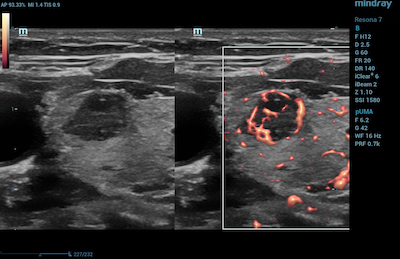

- Breast Imaging – CDI helps to determine the absence of flow in breast lesions. This is useful in distinguishing breast cancer from benign pathological conditions.

Color Doppler Ultra Micro Angiography of Breast Malginancy

Color Doppler Imaging of Breast Fibroadenoma